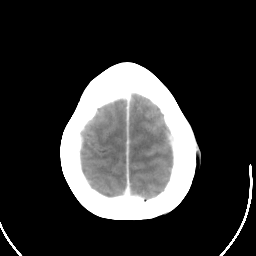

Metastatic bronchogenic carcinoma: Roentgen-ray CT (post-op) -- Slice #19

[Home][Help][Clinical] Slice 19